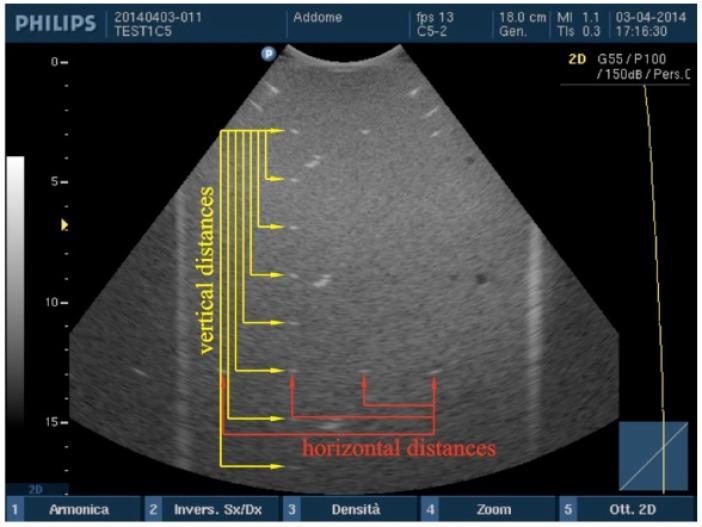

To check or to prevent failures in ultrasound medical systems, some tests should be scheduled for both clinical suitability and technical functionality evaluation: among them, image quality assurance tests performed by technicians through ultrasound phantoms are widespread today and their results depend on issues related to scanner settings as well as phantom features and operator experience. In the present study variations on some features of the B-mode image were measured when the ultrasound probe is handled by the technician in a routine image quality test: ultrasound phantom images from two array transducers are processed to evaluate measurement dispersion in distance accuracy, high contrast spatial resolution and penetration depth when probe is handled by the operator. All measurements are done by means of an in-house image analysis software that minimizes errors due to operator's visual acuity and subjective judgment while influences of ultrasound transducer position on quality assurance test results are estimated as expanded uncertainties on parameters above (measurement reproducibility at 95 percent confidence level): depending on the probe model, they ranged from ±0.1 to ±1.9 mm in high contrast spatial resolution, from ±0.1 to ±5.5 percent in distance measurements error and from ±1 to ±10 mm in maximum depth of signal visualization. Although numerical results are limited to the two examined probes, they confirm some predictions based on general working principles of diagnostic ultrasound systems: (a) measurements strongly depend on settings as well on phantoms features, probes and parameters investigated; (b) relative uncertainty due to probe manipulation on spatial resolution can be very high, i.e. from 10 to more than 30 percent;

为了检查或预防超声医疗系统出现故障,应安排一些测试,以评估临床适用性和技术功能:其中,技术人员通过超声体模进行的图像质量保证测试如今已广泛应用,其结果取决于与扫描仪设置、体模特征以及操作人员经验相关的问题。在本研究中,当技术人员在常规图像质量测试中操作超声探头时,测量了B模式图像某些特征的变化:对来自两个阵列换能器的超声体模图像进行处理,以评估操作人员操作探头时在距离精度、高对比度空间分辨率和穿透深度方面的测量离散度。所有测量均通过内部图像分析软件进行,该软件可将由于操作人员视力和主观判断导致的误差降至最低,同时将超声换能器位置对质量保证测试结果的影响估计为上述参数的扩展不确定度(95%置信水平下的测量再现性):根据探头型号,高对比度空间分辨率的不确定度范围为±0.1至±1.9毫米,距离测量误差的不确定度范围为±0.1至±5.5%,信号可视化最大深度的不确定度范围为±1至±10毫米。尽管数值结果仅限于所检查的两个探头,但它们证实了基于诊断超声系统一般工作原理的一些预测:(a)测量结果强烈依赖于设置以及所研究的体模特征、探头和参数;(b)由于探头操作导致的空间分辨率相对不确定度可能非常高,即从10%到超过30%;